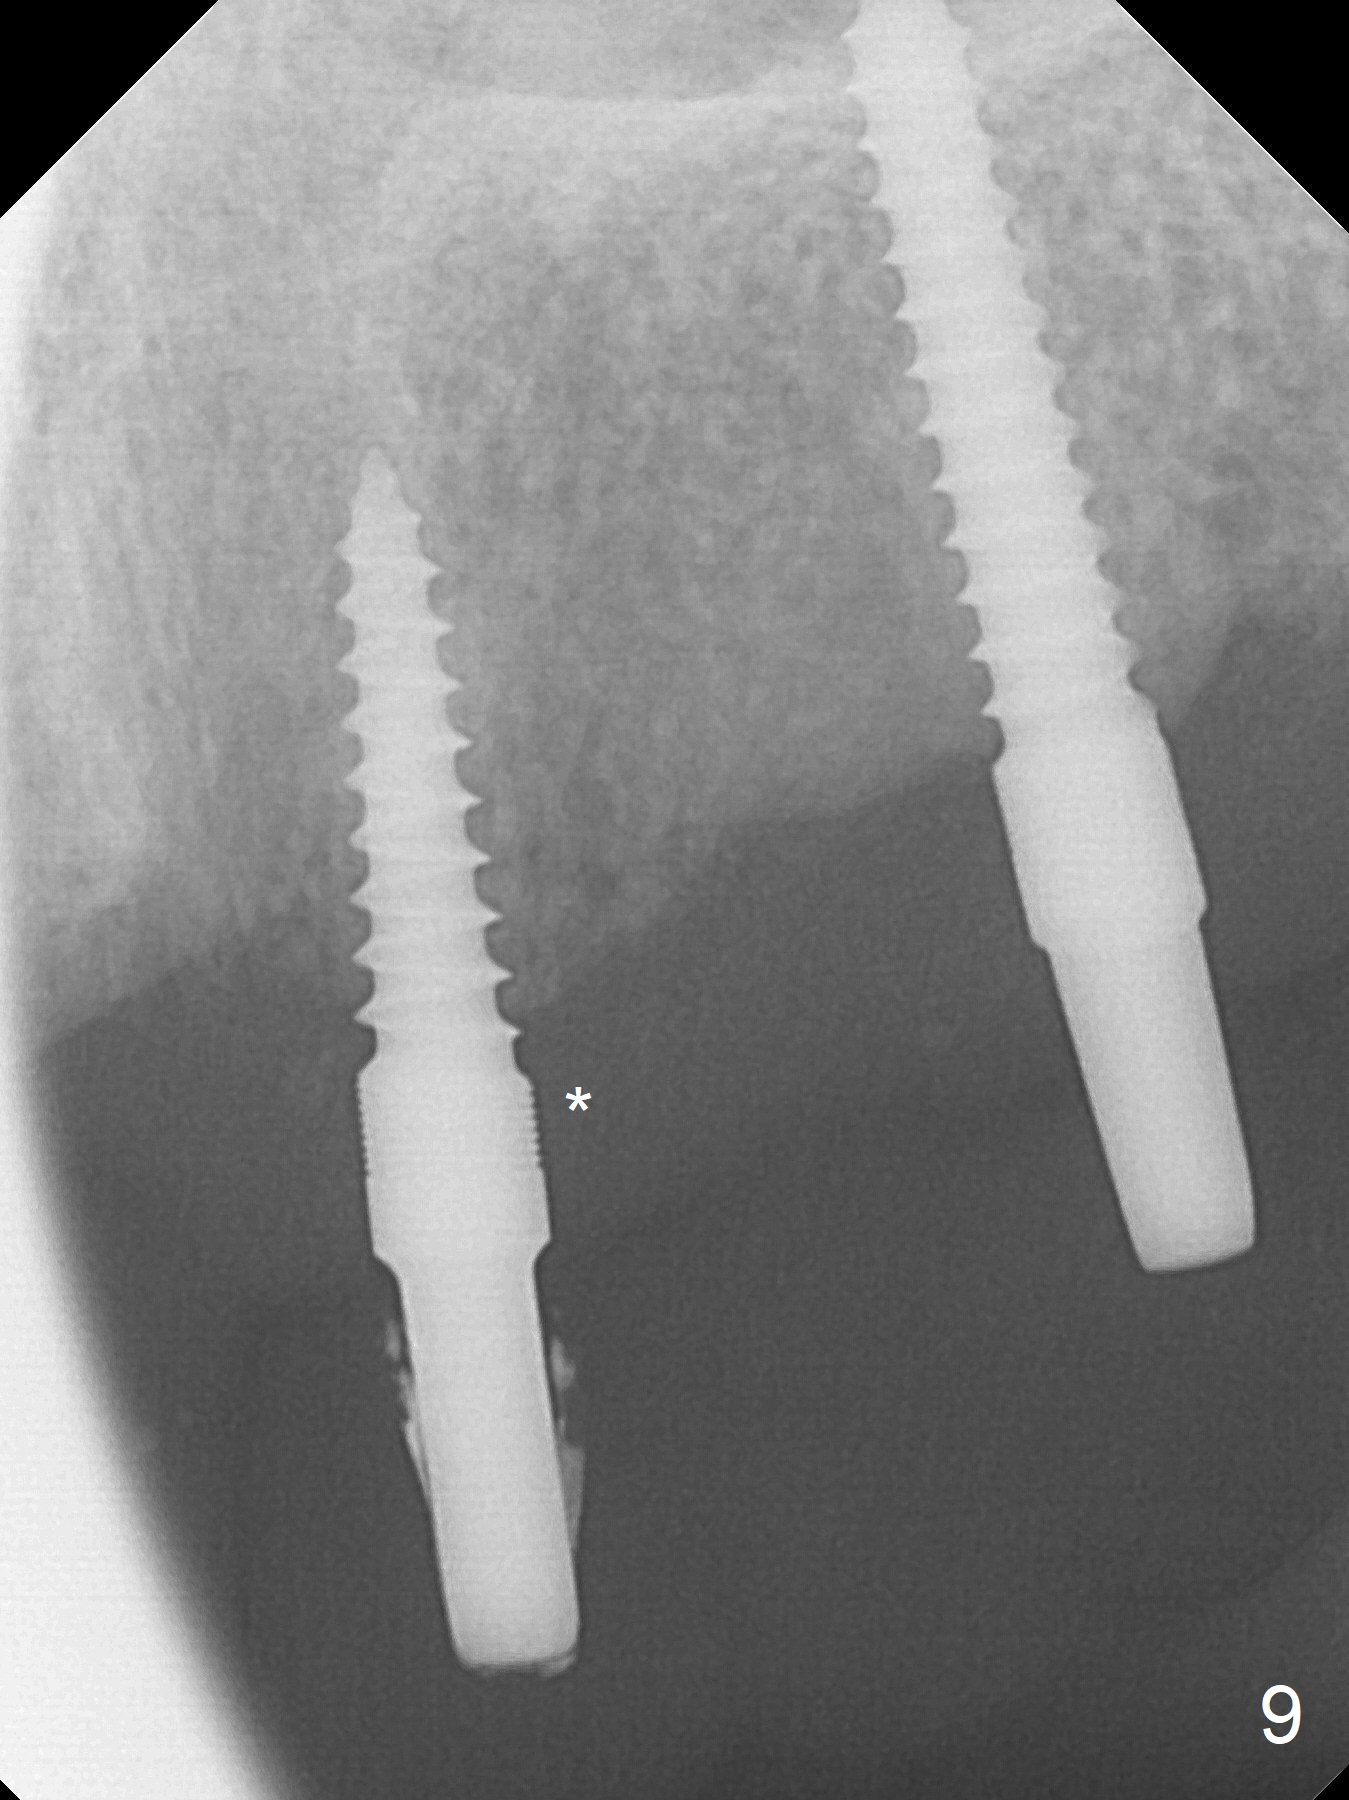

Incision reveals that the ridge at #9 and 11 is narrower than expected. A 3x14 mm 15º 1 piece implant is placed at the site of #9, while a 3x17 mm straight 1-piece one is placed at #11 (Fig.1,4). Insertion torques at #9 and 11 are 20 and 30 Ncm, respectively. The relatively low insertion torque is partially due to osteoporosis. The 65-year-old lady also has dry mouth. Osteotomy should be underprep. The position and trajectory of the implants are dictated by the partial denture (Fig.2). After minor abutment adjustment (Fig.3), an immediate provisional bridge is fabricated. There is no interference when the partial is removed and inserted. After bone graft (Fig.4 ^) and Osteogen Membrane, the ridge (Fig.3) is wider than before. The patient returns for reline 2 months postop (Fig.5-7). In spite of insufficient oral hygiene, the gingiva remains healthy around the implants. To form distinct papillae, acrylic should be added to (Fig.8 yellow line) and removed from (hushed area) the individual provisional crowns. One month after provisional modification (Fig.10, as compared to Fig.5), the pontic recipient site is concave (Fig.11) and becomes less concave after cord packing and abutment trimming. When the provisional bridge is reseated after impression (Fig.12), the pontic recipient site must be blanched again. Please trim the pontic recipient site of the model ~ .5 mm to enhance cosmetics. Water Pik has been used since surgery, but it may be related to loss of bone graft 3.5 months postop (Fig.9 *). One month post cementation, the patient has complained of pain when water pik is irrigating the gingiva palatal to the FPD, apparently in association with denture-related Candidiasis. Two weeks of use of Mycostatin Oral Suspension, peri-implantitis or peri-implant mucositis-like signs and symptoms disappear (Fig.13). CBCT taken 6 months postop confirms that the implants appear to be have been placed in the bone (14,15). The FPD appears to be loose 2.5 years post cementation.